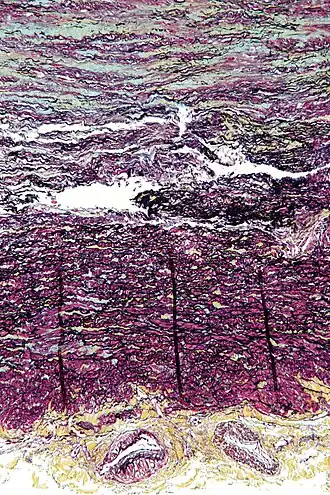

| Micrograph showing cystic medial degeneration, the histologic correlate of familial thoracic aortic aneurysms. The image shows abundant basophilic ground substance in the tunica media (blue at top of image) and disruption of the elastic fibers. The tunica adventitia (yellow at bottom of image) with vaso vasorum is also seen. Movat's stain. | |